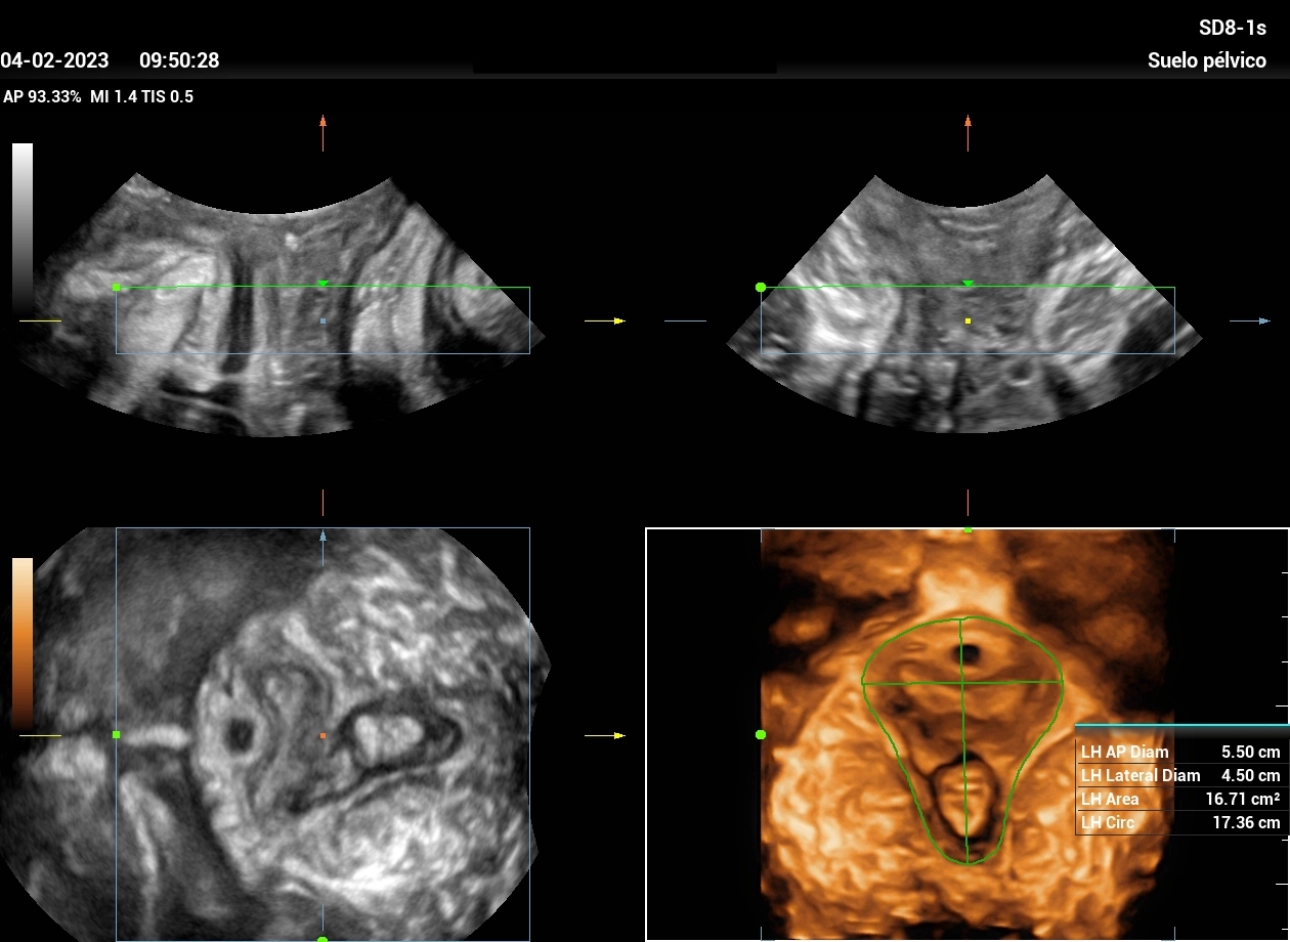

stress-urine-fig9

Figure 9: allows evaluation of the hiatus area in the coronal plane, with the automatic measurement software of the equipment.

stress-urine-fig10

Figure 10: Measurement of Levator Hiatus area in Valsalva maneuver, where we can appreciate a moderate increase of the area “Balloning” (31.52cm2); which does not generate symptoms in the patient, but enough to decrease contractility.